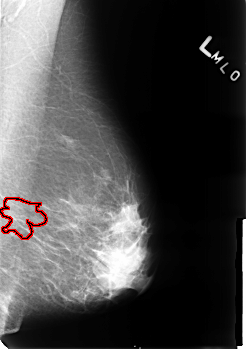

B_3243_1.LEFT_MLO

LEFT_MLO LINES 4528 PIXELS_PER_LINE 3192 BITS_PER_PIXEL 12 RESOLUTION 50 OVERLAY

FILE: B_3243_1.LEFT_MLO.OVERLAY

TOTAL_ABNORMALITIES 1

ABNORMALITY 1

LESION_TYPE MASS SHAPE ASYMMETRIC_BREAST_TISSUE MARGINS N/A

ASSESSMENT 2

SUBTLETY 5

PATHOLOGY BENIGN_WITHOUT_CALLBACK

TOTAL_OUTLINES 1

BOUNDARY